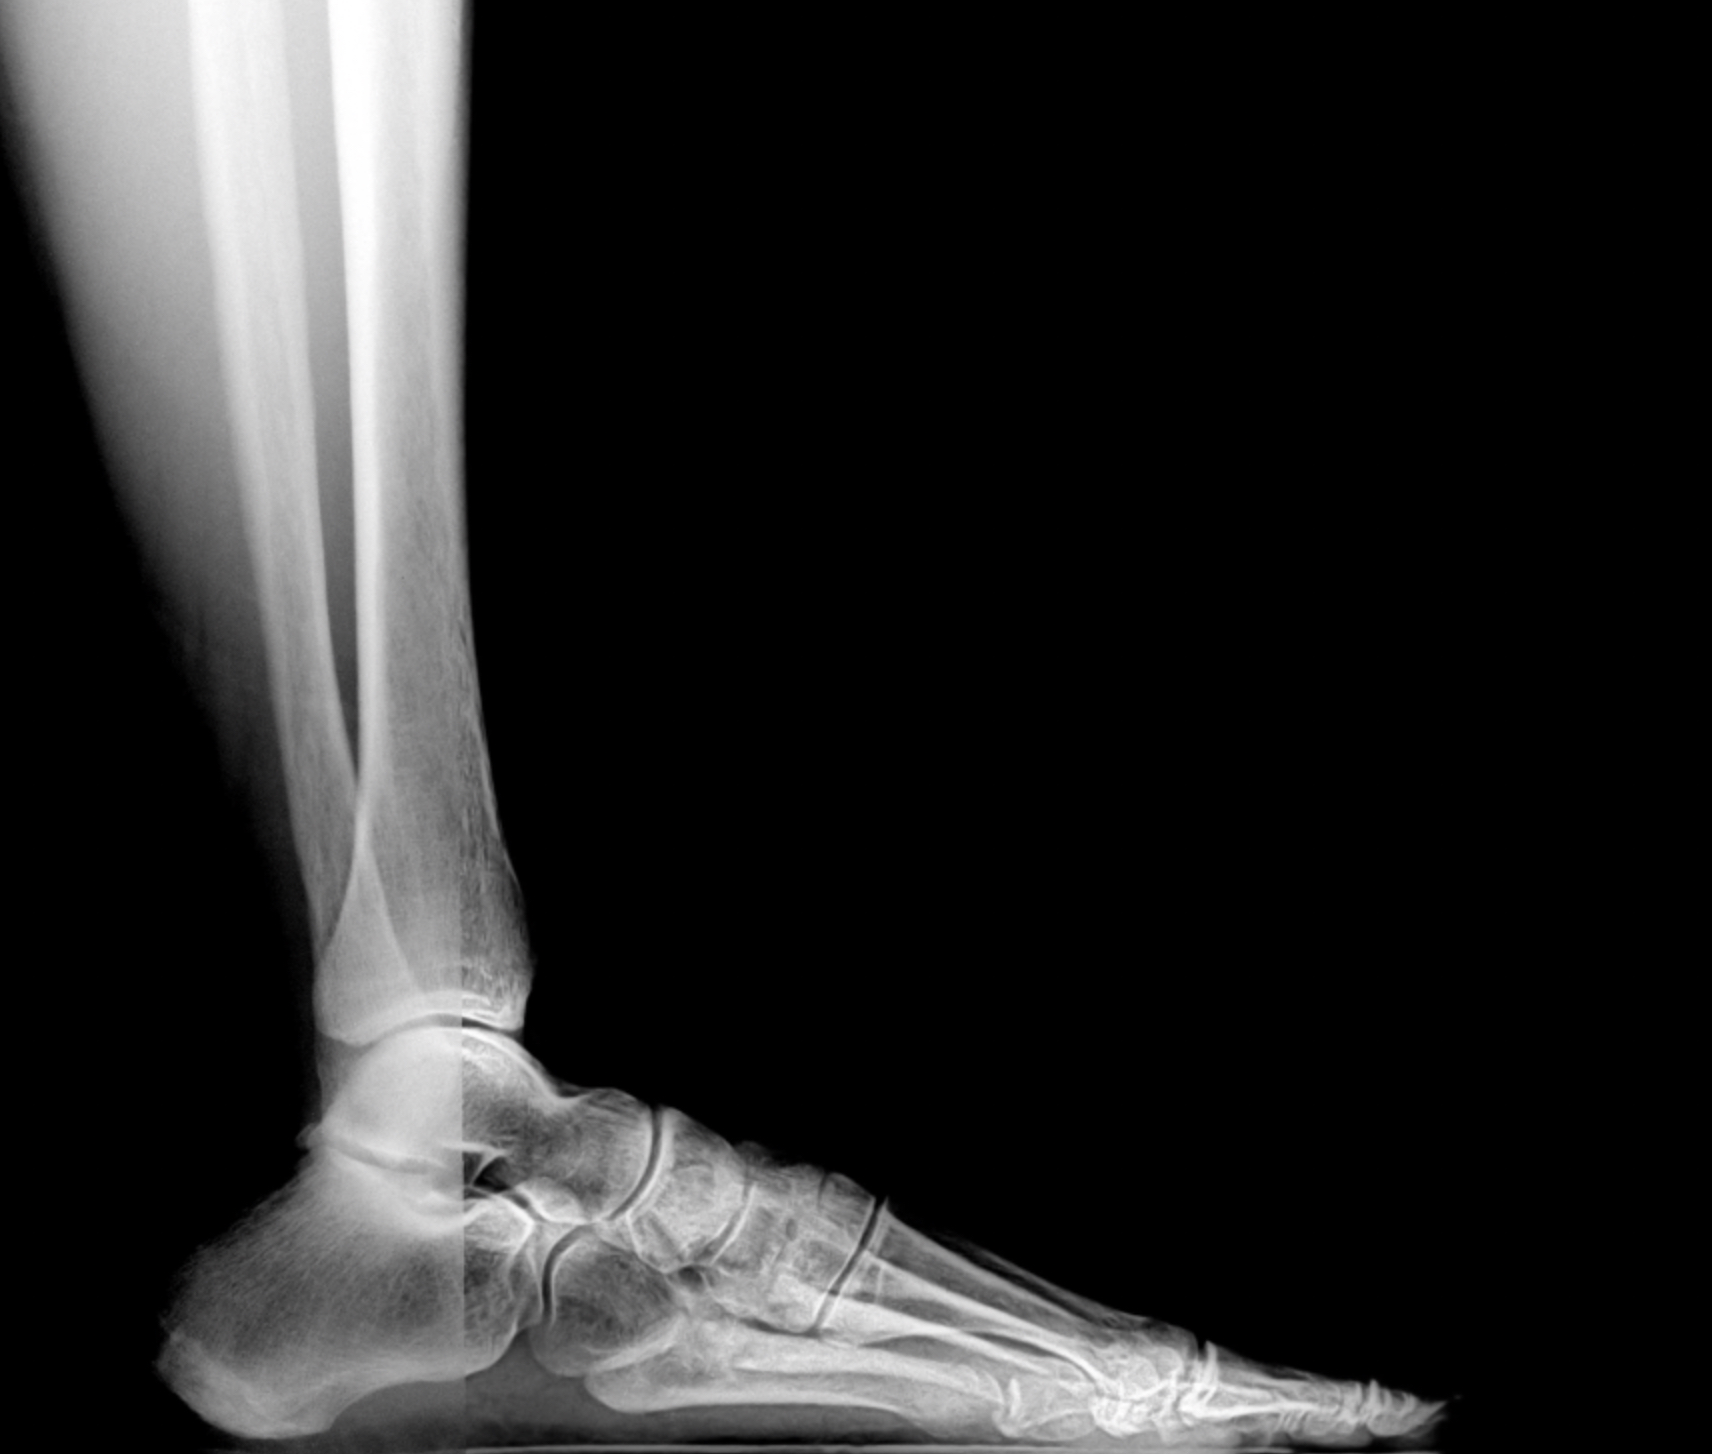

Pre-op XR Images